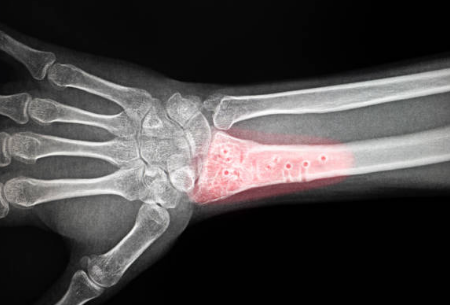

뼈의 손상

골다공증으로 인해 뼈가 더 쉽게 손상되어 골절이나 골대 손상이 발생할 수 있습니다.

골다공증이 진행되면 어떤 위험이 있나요?

골절, 만성 통증, 신체 활동 제한 등이 발생할 수 있으며, 골절이 회복되지 않을 경우 심각한 합병증이 생길 수 있습니다.